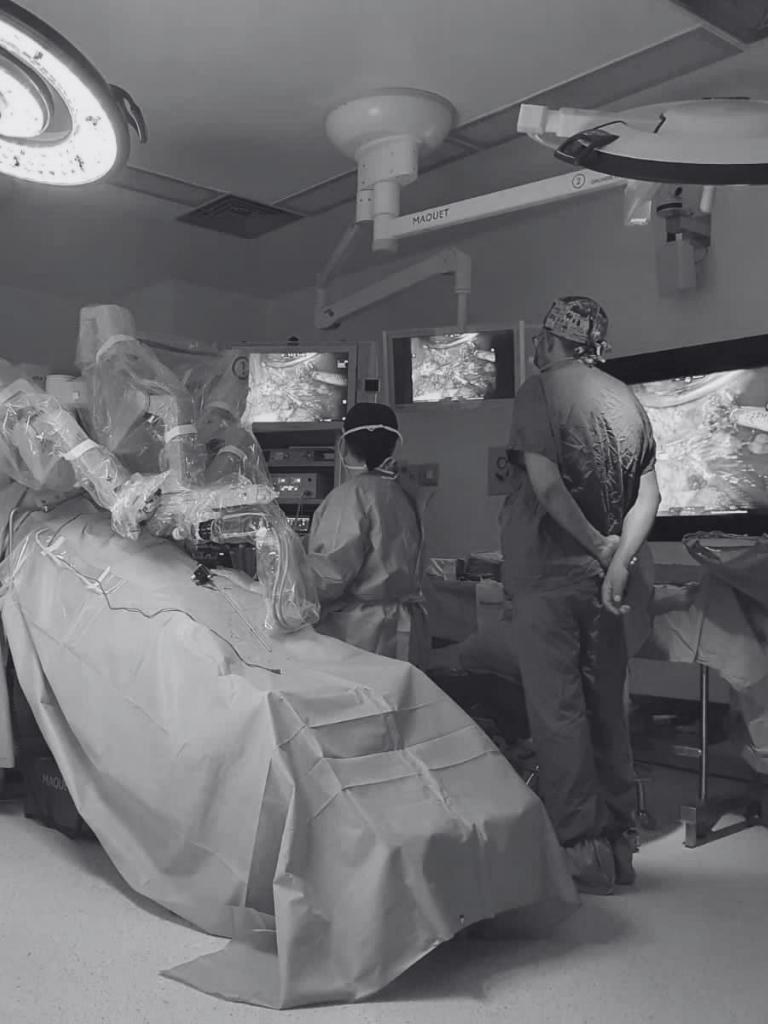

La cirugía robótica o asistida por robot, permite a los cirujanos hacer muchos tipos de procedimientos complejos con mayor precisión, flexibilidad y control en comparación con las técnicas convencionales.

El sistema robótico cuenta con un brazo para la cámara y 3 brazos mecánicos, e instrumentos quirúrgicos montados en ellos. El cirujano controla los brazos mientras está sentado frente a una consola de computadora cerca de la mesa quirúrgica. La consola proporciona al cirujano una visión tridimensional aumentada de alta definición del sitio quirúrgico.